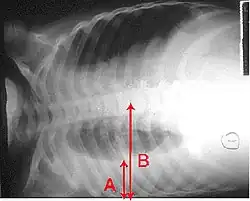

A pleural effusion appears as an area of whiteness on a standard posteroanterior chest X-ray.[15] Normally, the space between the visceral pleura and the parietal pleura cannot be seen. A pleural effusion infiltrates the space between these layers. Because the pleural effusion has a density similar to water, it can be seen on radiographs. Since the effusion has greater density than the rest of the lung, it gravitates towards the lower portions of the pleural cavity. The pleural effusion behaves according to basic fluid dynamics, conforming to the shape of pleural space, which is determined by the lung and chest wall. If the pleural space contains both air and fluid, then an air-fluid level that is horizontal will be present, instead of conforming to the lung space.[16] Chest radiographs in the lateral decubitus position (with the patient lying on the side of the pleural effusion) are more sensitive and can detect as little as 50 mL of fluid. Between 250 and 600mL of fluid must be present before upright chest X-rays can detect a pleural effusion (e.g., blunted costophrenic angles).[17]

Chest computed tomography is more accurate for diagnosis and may be obtained to better characterize the presence, size, and characteristics of a pleural effusion. Lung ultrasound, nearly as accurate as CT and more accurate than chest X-ray, is increasingly being used at the point of care to diagnose pleural effusions, with the advantage that it is a safe, dynamic, and repeatable imaging modality.[18] To increase diagnostic accuracy of detection of pleural effusion sonographically, markers such as boomerang and VIP signs can be utilized.[19]